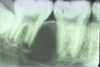

what type of pa is this

mx canine

you want to see the mesial contact of canine